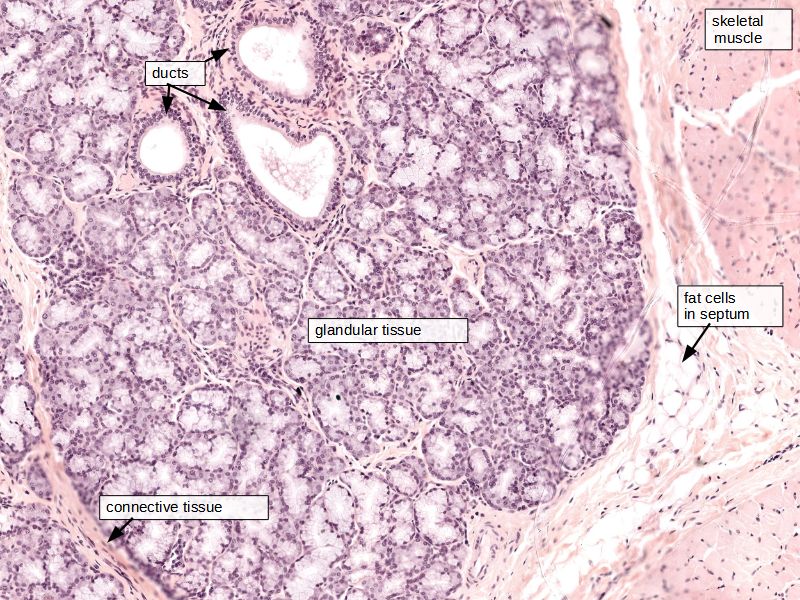

Fill in all the missing labels, and assess as you move through the slides. Answers on the down slide. It is important to do this using pen and paper, and not just glance through the images.